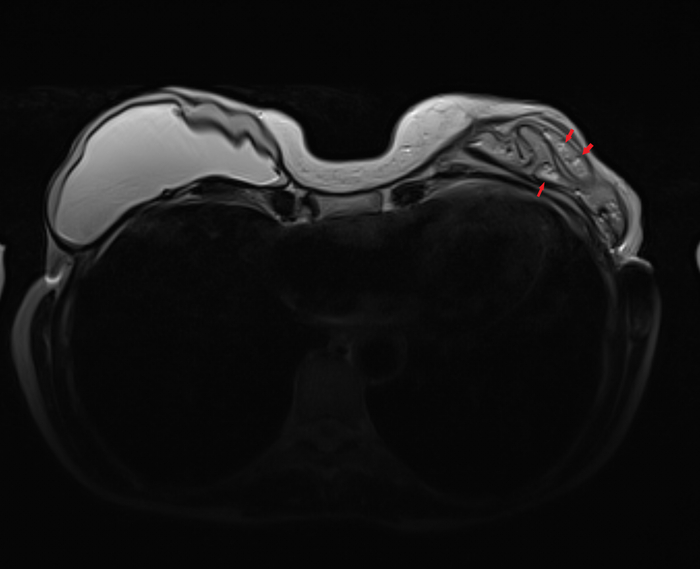

Пациентка, 64 года, перенесла двустороннюю мастэктомию (удаление обеих молочных желёз) по поводу рака 14 лет назад с пластикой с обеих сторон двухкамерные имплантами. Сейчас клинически подозревают фиброз капсулы и возможно разрыв левого импланта. Для подтверждения диагноза провели МРТ молочных желёз (только нативную часть протокола, т.е. без в/в введения контрастного вещества, от которого пациентка отказалась).

где центрально расположена камера, заполненная физ.раствором (голубой цвет), на периферии - камера, заполненная силиконом (красный цвет), и отграничено это всё фиброзной капсулой, которой тело старается отграничить инородный объект (пунктирная линия):

если мы сравним правый имплант с левым, то разница очевидна, тут не надо быть рентгенологом, чтобы понять что что-то тут не то, а именно сам имплант меньше, интенсивность сигнала иная (цвет более тёмный) + видны какие-то линии внутри импланта (красные стрелочки):

Линии эти - так называемый признак "лингвини" (или по-английски linguine sign), т.к. похожи они на одноимённую итальянскую пасту лингвини:

и являются ни чем иным как спавшимися стенками камер имплантов, что указывает на внутрикапсульный (в пределах образовашейся фиброзной капсулы) разрыв импланта, но без свободного выхода содержимого в окружающие мягкие ткани.

Интенсивность сигнала поменялась из-за того, что физ.раствор частично смешался с силиконом, и вследствие этого определяются пузырьки физ.раствора в силиконе - т.н. признак "салатного масла" или "salad oil sign" (капли, как при добавлении масла в воду):

которые я отметил красными стрелочками:

и на секвенции с подавлением воды, которая становится на картинке "чёрной" (синяя звёздочка), а силикон остаётся "белым" (красная звёздочка):

Имплант, соответственно, больше не жизнеспособен и его следует заменить.